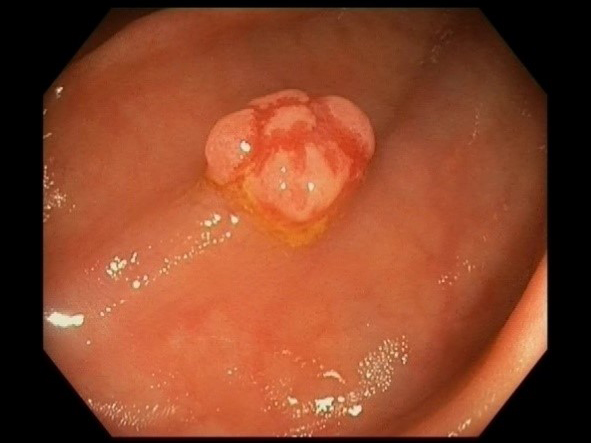

Sessile Polyp from the right colic flexure of a 68-year-old female with Crohn’s disease.

A 68-year-old female with known Crohn’s disease underwent surveillance colonoscopy. A four millimetre sessile polyp was detected at the right colonic flexure and removed endoscopically (Panel A).